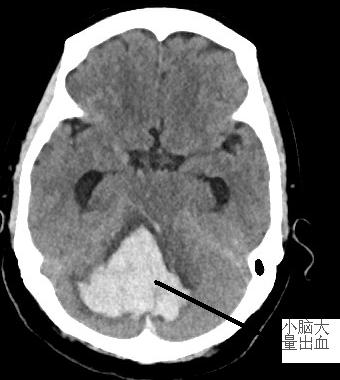

患者徐阿婆,71歲,3月13日約11時(shí)被發(fā)現(xiàn)躺于田野中,呼之不應(yīng)。家屬趕緊將其送至我院急診科。通過腦部CT掃描出小腦大量出血,出血量約30ml,小腦半球、小腦蚓、腦干(生命中樞)受壓,環(huán)池變窄,且患者處于昏迷狀態(tài),雙側(cè)瞳孔對(duì)光反射遲鈍,情況危急。為搶救生命,需要進(jìn)行開顱手術(shù)治療。我院神經(jīng)外科醫(yī)生謝志芳告知家屬病情后,家屬考慮到徐阿婆年紀(jì)較大、經(jīng)濟(jì)狀況不佳等情況,對(duì)是否進(jìn)行手術(shù)猶豫不決。

左圖為術(shù)前顱內(nèi)血腫,右圖為術(shù)后原血腫位置。

復(fù)查CT后,徐阿婆小腦內(nèi)血腫基本清除,壓力下降。后續(xù)在我院神經(jīng)外科與福醫(yī)大附二院神經(jīng)外科專家聯(lián)合治療下,病情好轉(zhuǎn),4月12日痊愈出院。